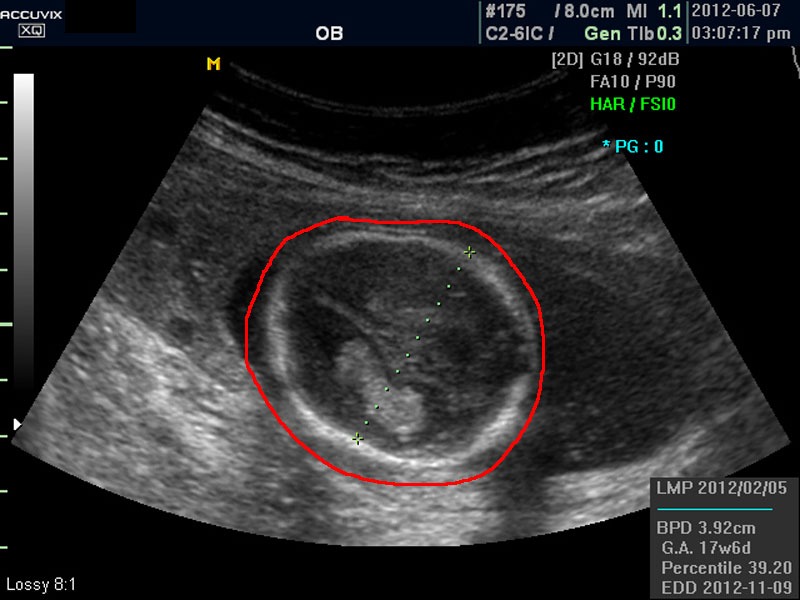

화면에서 좌측이 태아 머리 부분으로 빨간 펜으로 표시되어 있습니다.

초음파 상 태아의 머리가 좌측인가 우측인가 하는 것은 초음파 탐촉자의 위치를 어디에 두었느냐에 따라 다른 것 뿐으로 화면상 어디 위치하는 지는 중요하지 않습니다.

위 사진에서 빨간 동그라미로 표시한 부분이 태아의 머리를 위에서 내려다 본 수평 단면입니다.

하얗게 보이는 것은 뼈이고 내부에 검게 보이는 것은 뇌실에 고인 척수액 부분이며 내부의 하얀 부분은 뇌조직과 뇌실 내 맥락막이라고 하는 것입니다.

4. BPD

Biparietal Diameter의 약자로 머리를 위에서 보아서 양쪽 옆통수에서 반대쪽 옆통수까지의 길이입니다.

이는 임신 중기부터 후기까지 태아의 발육을 판단하는 중요한 지표이며 태아의 체중을 예측하는 데 쓰이는 지표 중 하나입니다.